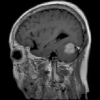

4.1.6 Brain MRI

Brain tumors pose significant health challenges, often impacting critical functions such as vision, balance, and cognition. Early detection is crucial for improving patient outcomes and quality of life. Through MRI scans, different conditions of the brain can be visually detected. The selected brain tumor dataset 666https://www.kaggle.com/datasets/sami009mr/brain-tumor-dataset contains 3,362 images across four categories: glioma, meningioma, pituitary tumors, and normal brains. Images illustrating the three aforementioned classes can be found in Fig. 7.

Table 1 provides a detailed summary of the datasets used in this study, highlighting the total number of images in each dataset, the distribution between training and testing sets, and the specific classes represented. Each dataset corresponds to a particular medical imaging domain with distinct classes relevant to diagnosing specific conditions. Also, Fig. 9 presents a representative image from each dataset, allowing for a visual comparison of the diverse tones, patterns, and textures present across the datasets. Such diversity in visual characteristics highlights the need for a robust model that can handle all image characteristics.